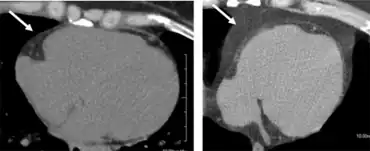

Mid LV slice from a noncontrast CT of heart indicating the epicardial fat distribution in individual without metabolic syndrome arrow left and individual with known metabolic syndrome arrow right